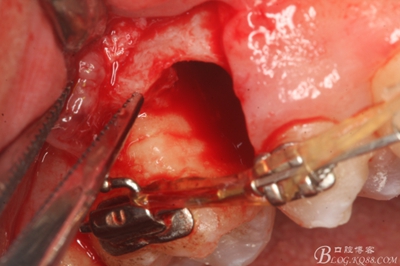

圖13. 用小球鉆去除約1mm牙槽骨,暴露15牙根面約5mm。

圖14.用小球鉆縱分15牙根